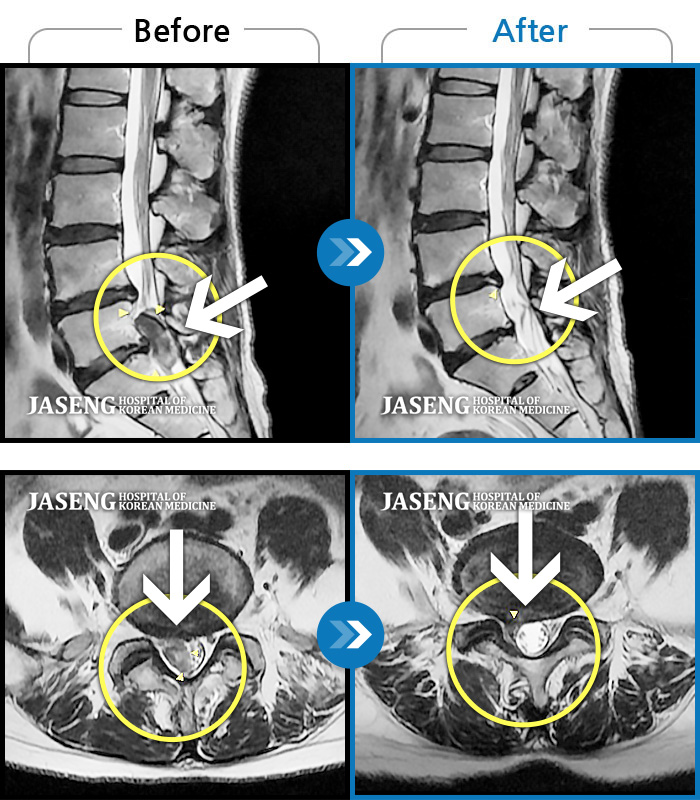

허리디스크

해운대 · 이상건 원장

허리 골반통증 및 우 하지 방산통

촬영시기

2017.05.29 ~ 2017.12.27